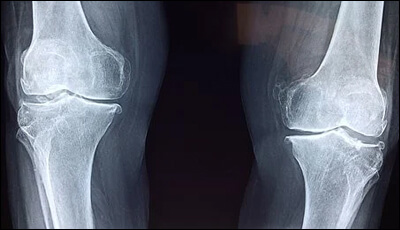

프로폴리스는 뼈조직을 튼튼하게 하고 골밀도를 높이는데 도움을 주는 카페인산 페네틸에스터라는 성분이 풍부하게 들어있습니다. 이 성분은 항염, 항암에도 효과적인 물질로 뼈의 염증을 예방하는 역할을 하므로 관절염, 골다공증 등을 앓는 분들에게 좋다고 합니다. 해외 연구결과에 따르면 프로폴리스가 연골조직 생성에 도움을 준다고 하니 뼈 건강 개선에 관심 있는 분들이라면 눈여겨보시기 바랍니다.